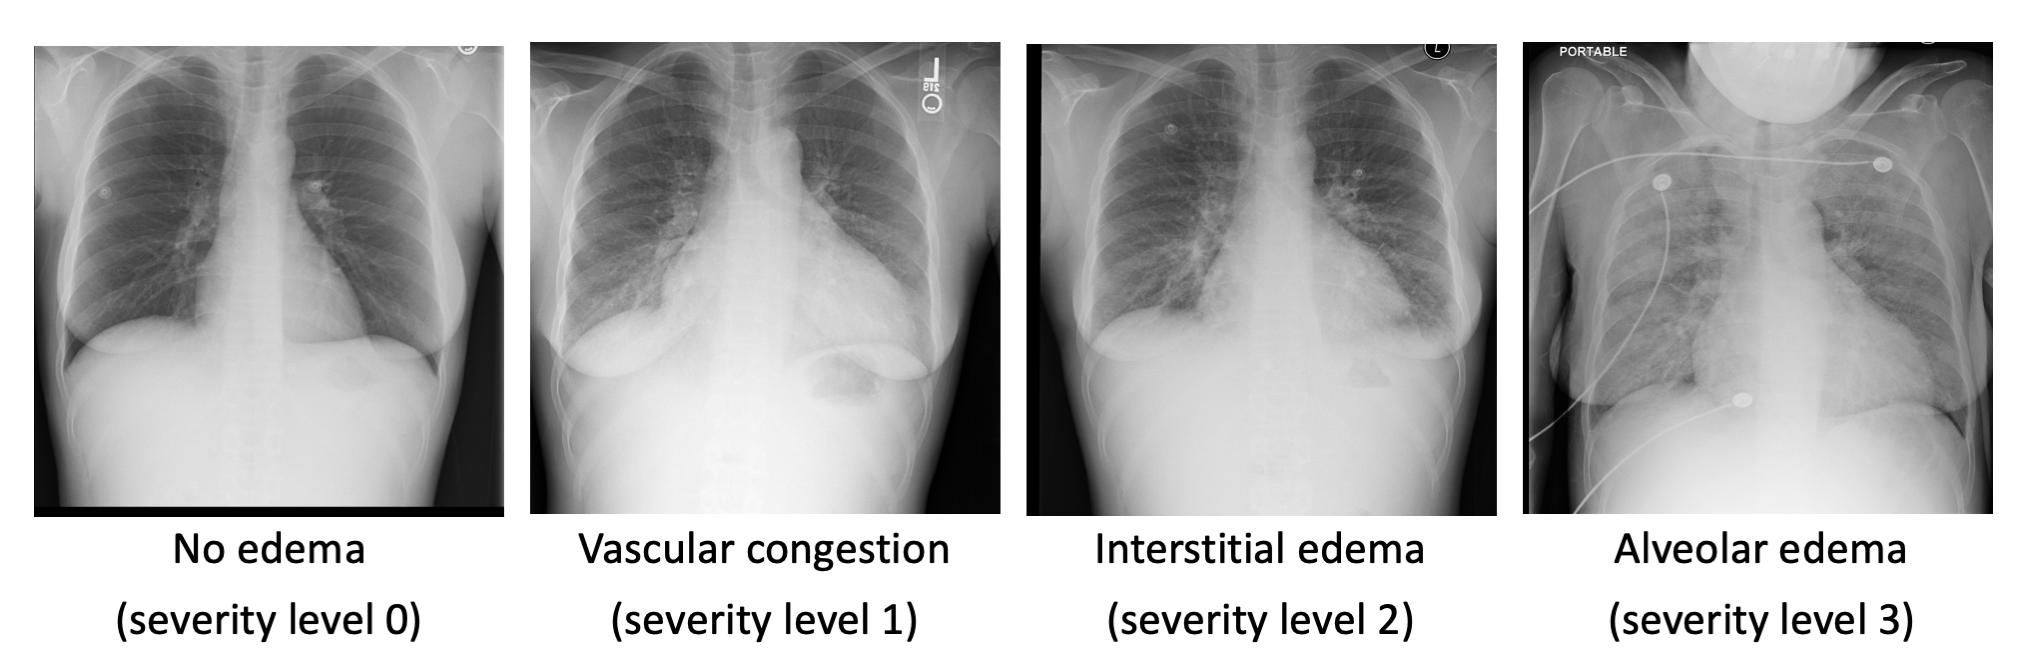

To support better clinical decision-making for heart failure patients and enable quantitative research on efficacy of treatments, We are developing machine learning algorithms to automatically and quantitatively assess the severity of pulmonary edema from chest x-ray images.

Representative chest x-ray images of pulmonary edema: